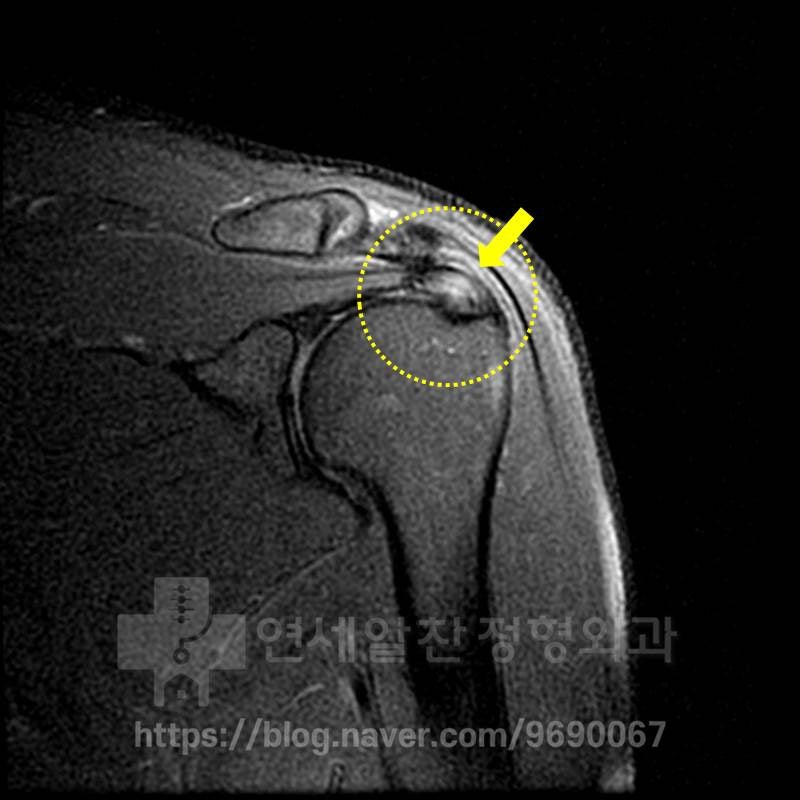

MRI 상에서 극상근 부위에 정상적으로는 검게 보여야 할 인대가 하얗게 보이면서 심한 염증소견이 보이고 있습니다. 이것을 심한 건증(인대가 약해진것)으로 판단하고 이것에 대한 봉합술을 권고 받은 것으로 보입니다. 하지만 자세히 보면 MRI 상에서 극상근 안에 조그만 까만 점이 보이는 것이 보이며 미세한 석회로 생각됩니다. 그래서 초음파 검사를 통해 다시 한번 확인해 보기로 하였습니다.